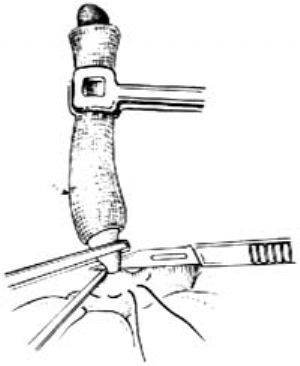

12.8 8.切斷闌尾

在刀刃上塗純石炭酸後,刀刃向上,緊貼闌尾根部夾緊的直止血鉗下面,切斷闌尾,將刀及闌尾一併棄去[圖1 ⑺]。

圖1 ⑺切斷闌尾

12.10 10.包埋闌尾殘端

助手用左手持無齒鑷提起荷包縫線線頭對側的盲腸壁,右手持夾住線結的止血鉗,將闌尾殘端推進盲腸腔內,同時術者上提並收緊荷包縫線,使殘端埋入荷包口,結紮後剪斷線頭[圖1 ⑼]。

圖1 ⑼包埋殘端

圖1 ⑼包埋殘端

有人主張不包埋殘株,僅用絲線結紮闌尾根部即可,用此法時最好用縫針稍縫一點闌尾漿膜再結紮闌尾以免滑脫,此針縫合勿穿過闌尾腔。在闌尾周圍盲腸壁明顯水腫質脆時,不宜勉強做荷包埋沒殘株,只做單純結紮更爲安全。如擬用周圍組織覆蓋闌尾殘端,可用闌尾系膜殘緣或附近腸脂垂,切勿牽拉大網膜與殘端固定。